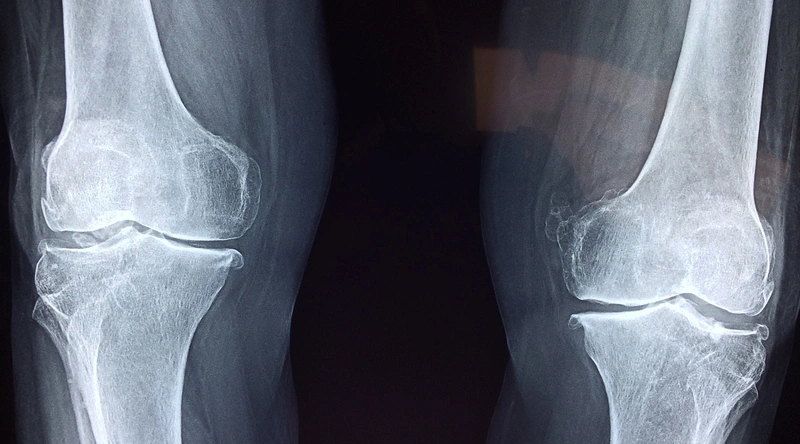

관절염은 주로 노화, 유전적 요인, 잘못된 자세, 비만 등 여러 가지 원인에 의해 발생합니다. 특히, 퇴행성관절염은 시간이 지남에 따라 관절의 연골이 마모되고, 이로 인해 통증과 염증이 발생하는 질환입니다. 또한, 외상이나 감염 등도 관절염의 원인이 될 수 있습니다. 이러한 원인으로 인해 발생하는 관절염의 증상은 통증, 부기, 운동 범위의 제한 등으로 나타납니다.

관절염의 증상은 개인에 따라 다르게 나타날 수 있으며, 날씨 변화나 활동량에 따라 증상이 악화될 수도 있습니다. 초기에는 경미한 통증으로 시작되지만, 시간이 지나면서 점차 심해질 수 있습니다. 따라서 이러한 증상이 지속된다면 조기에 전문가의 진단을 받는 것이 중요합니다.